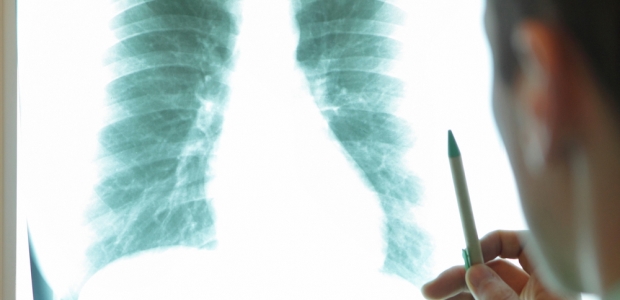

The report describes a cluster of 60 cases of PMF identified in current and former coal miners at one Eastern Kentucky radiology practice during January 2015–August 2016, a cluster that was not uncovered by the national surveillance program.